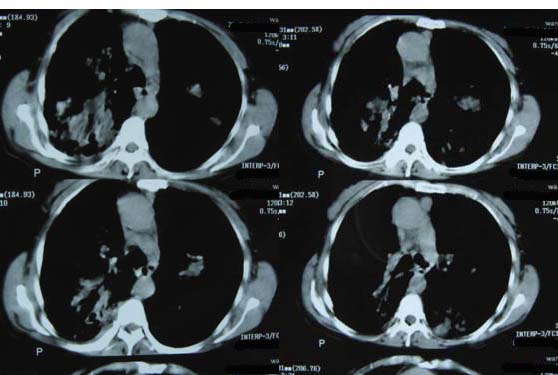

标题: CT8382:男,75,咳嗽,咳血有半年时间。 [打印本页]

标题: CT8382:男,75,咳嗽,咳血有半年时间。

右肺下叶弥漫性片状增高影 纤维组织增生   左肺上叶尖段大结节样增高影边界清楚 中叶下叶大片增高影(内可见钙化)

1.吸入性肺炎(真菌性)

2.干酪型肺炎

3.继发性肺结核?